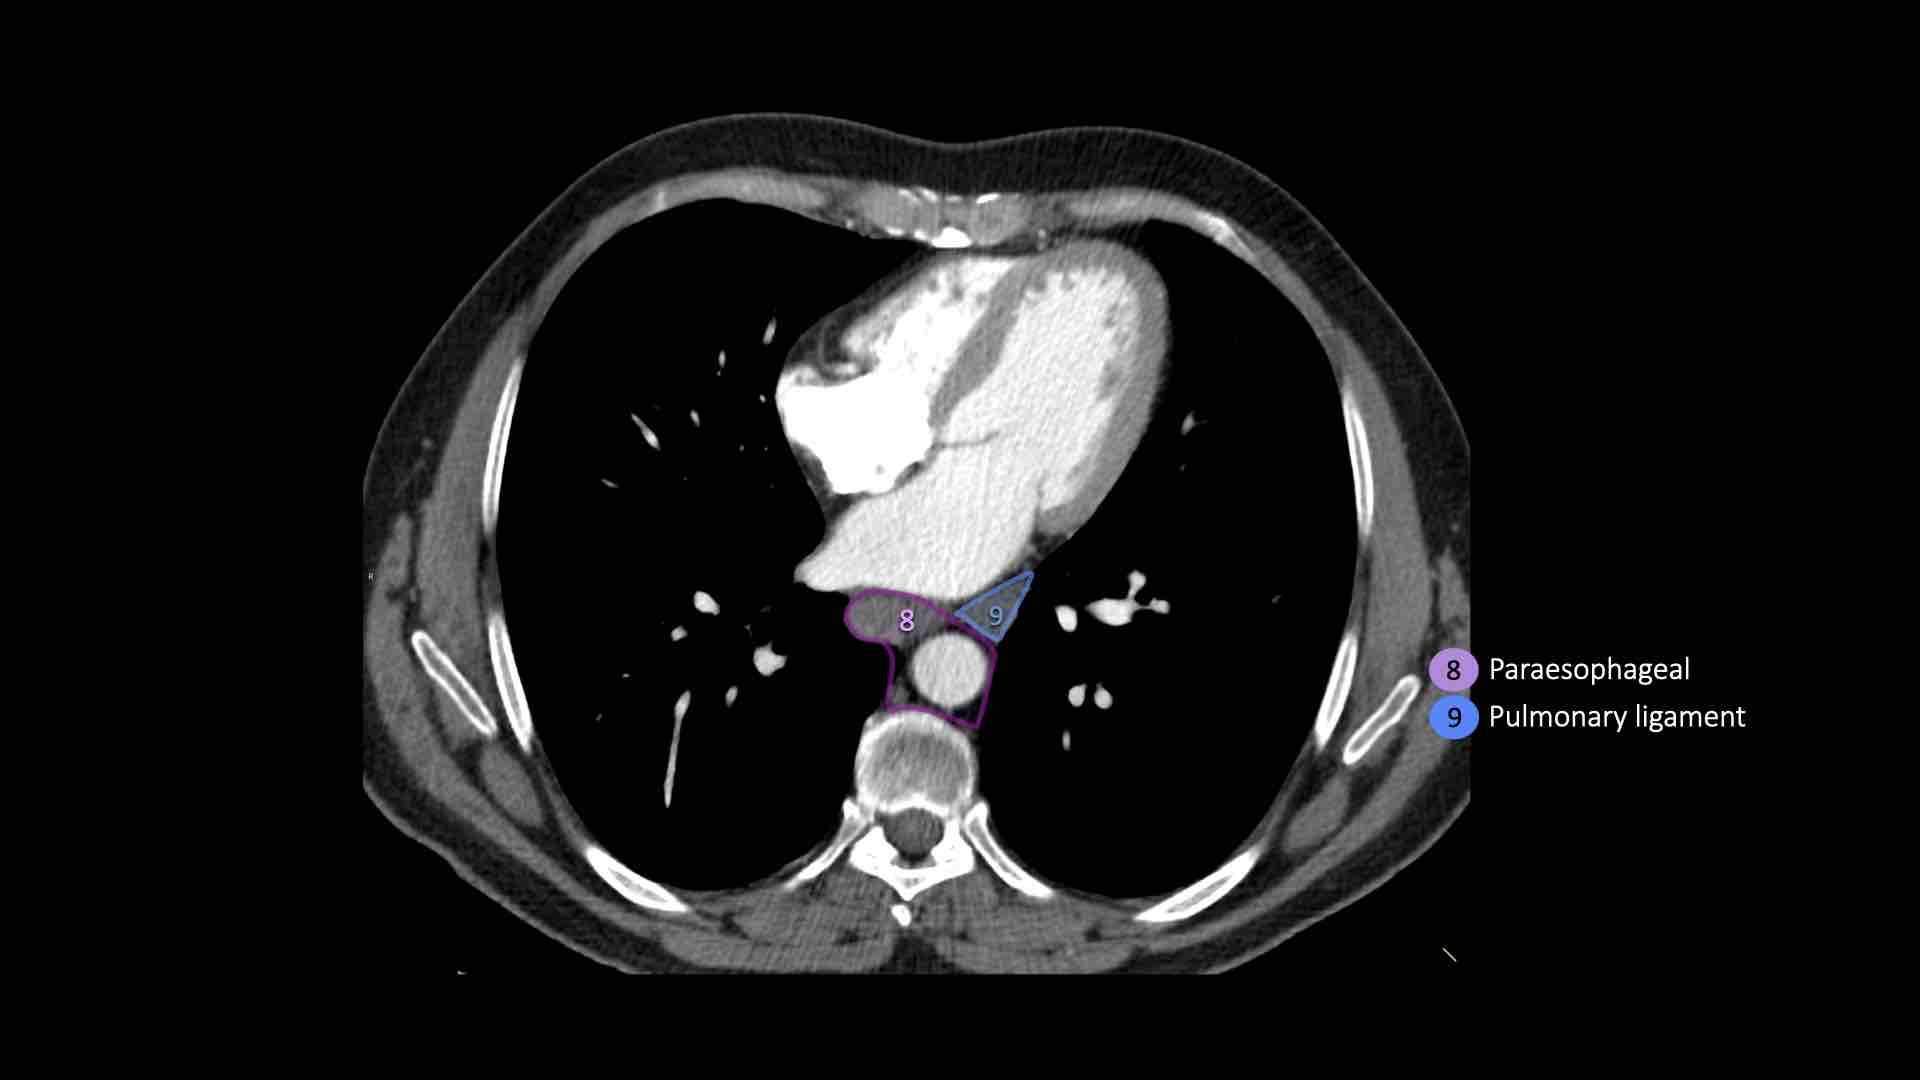

9. Dây chằng phổi

Các hạch nằm trong dây chằng phổi.

9. Hạch dây chằng phổi

Hạch dây chằng phổi nằm trong dây chằng phổi, bao gồm các hạch ở thành sau và phần dưới của tĩnh mạch phổi dưới.

Dây chằng phổi là phần kéo dài xuống dưới của các nếp gấp màng phổi trung thất bao quanh rốn phổi.

EUS đặc biệt hữu ích trong việc tiếp cận các hạch ở trung thất dưới (nhóm 7, 8 và 9).